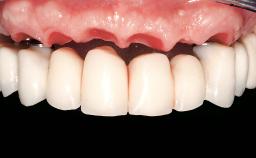

Immediate Loading of Eight Implants in the Maxilla and Six Implants in the Mandible and Final Restoration with Three-Unit and Four-Unit FDPs

German Gallucci, Jean-Pierre H Bernard, Urs C Belser